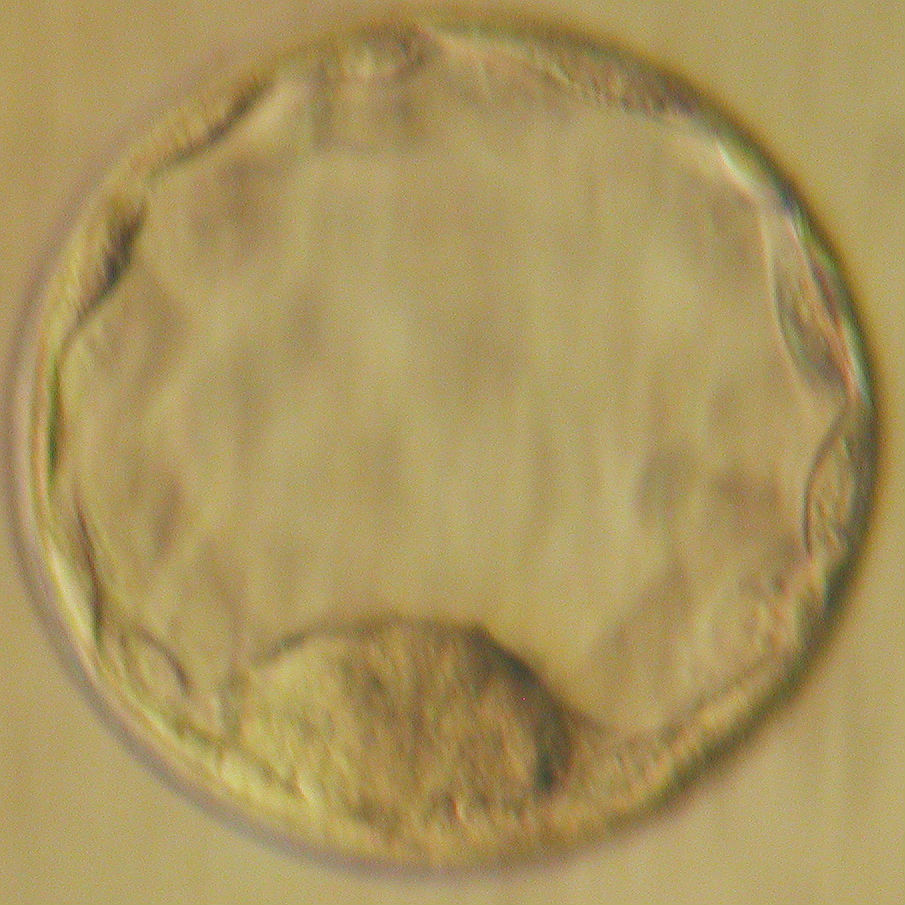

Визуально бластоциста на 5 день под микроскопом выглядит как пузырёк с жидкостью и группой клеток, которые постепенно организуются в будущие ткани.

Фотографии бластоцисты на 5 день помогают врачам и исследователям оценить качество эмбриона перед его возможной имплантацией.

Микроскопические изображения бластоцисты помогают медицинским специалистам исключить возможные аномалии и выбрать самые здоровые эмбрионы для трансплантации.

Бластоциста и эмбрион 7 дня развития